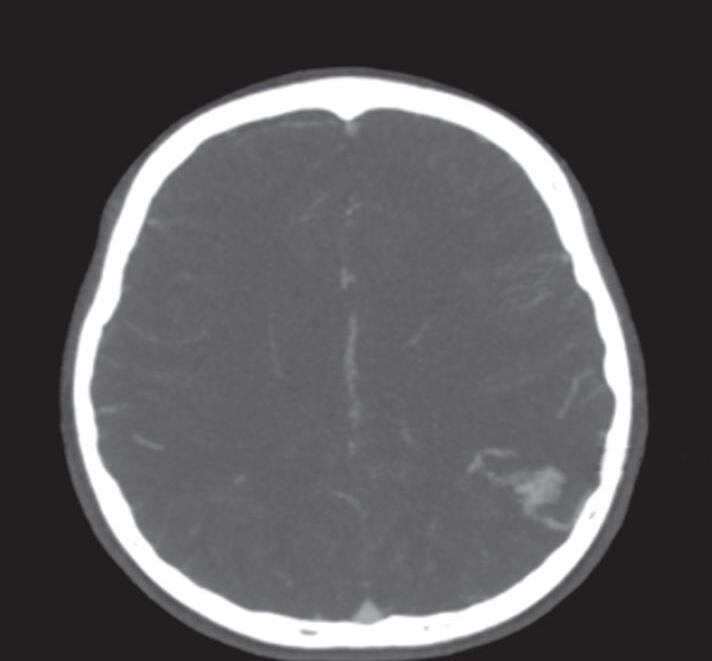

A suspeita diagnóstica das MAVs geralmente é feita por meio de métodos não invasivos de aquisição de imagem, tais como tomografia computadorizada (TC), angiotomografia, ressonância magnética (RNM) e angiorressonância, contudo, as informações anatômicas vasculares necessárias para o planejamento e a execução terapêutica demandam geralmente do estudo dinâmico da angioarquitetura da MAV pela arteriografia cerebral, considerado o exame padrão-ouro para o diagnóstico (Figs. 1-21 e 1-22).35

Em virtude de as manifestações clínicas não serem exclusivas das MAVs, a tomografia computadorizada do crânio sem contraste

é geralmente o primeiro exame realizado na investigação diagnóstica. Algumas alterações presentes nessa tomografia, associadas à história clínica do paciente podem direcionar a suspeição diagnóstica; são eles: pacientes jovens com hemorragia intraparenquimatosa lobar espontânea, sangramento inexplicável intraventricular ou subaracnóideo, presença de calcificações curvilíneas ou salpicadas, ou imagens serpiginosas espontaneamente hiperdensas, que podem corresponder a vasos anômalos integrantes do nidus, a veias de drenagem ou a artérias nutridoras dilatadas. Embora a angiotomografia possibilite uma melhor visualização das estruturas vasculares, a ressonância magnética em contrapartida, permite melhor

Fig. 1-21. TC de crânio sem contraste em cortes (a) axial e (b) coronal. (c) RNM encéfalo T1 com contraste axial. (d) Angiorressonância arterial sagital. Arteriografia digital em (e) AP e (f) perfil, demonstrando MAV não rota localizada no giro pré-central à esquerda nutrida por ramos da artéria cerebral média e caloso marginal esquerdo. Setas azuis apontando para o nidus da MAV.

Fig. 1-22. RNM encéfalo FLAIR (a) axial e (b) sagital mostrando hipossinal no sulco central à esquerda. MAV não rota localizada no sulco central à esquerda (seta azul). (c) Imagem intraoperatória mostrando veia arterializada, dilatada localizada no sulco central esquerdo (seta vermelha).

visualização da anatomia cerebral, das alterações parenquimatosas, bem como: gliose peri ou intranidal, atrofia parenquimatosa com dilatação focal do sistema ventricular, possibilita a diferenciação da hemorragia aguda da crônica (visualização da hemossiderina nas sequências gradiente eco [GRE] e hidrocefalia (secundária a hemorragia prévia e ou compressão do sistema ventricular por veias de drenagem dilatadas).35